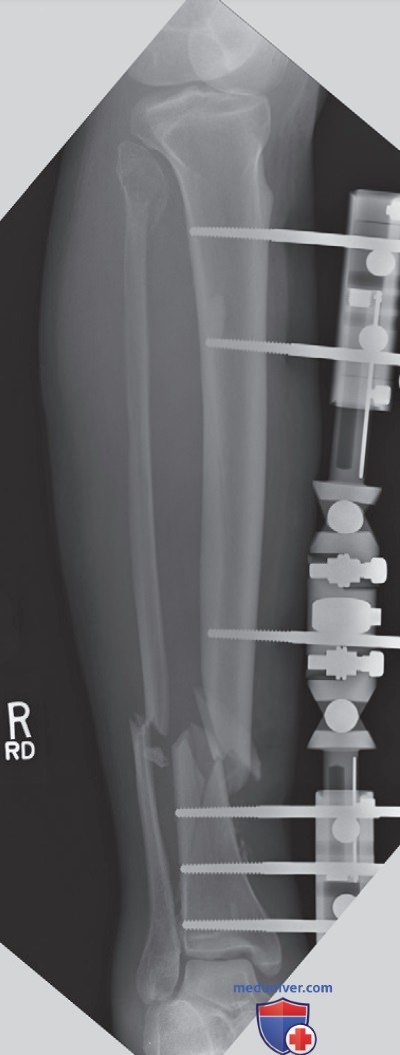

Рисунок 7. Рентгенография правой голени в ПЗ проекции при травме. Сустав, располагающийся ближе к перелому, был уложен правильно.

Если при исследовании длинных костей должны визуализироваться два смежных сустава, но из-за перелома расположить оба сустава оптимально не удается, необходима оптимальная укладка сустава, находящегося ближе к перелому (рис. 7).